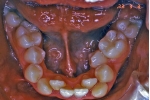

マルチブラケット終了時